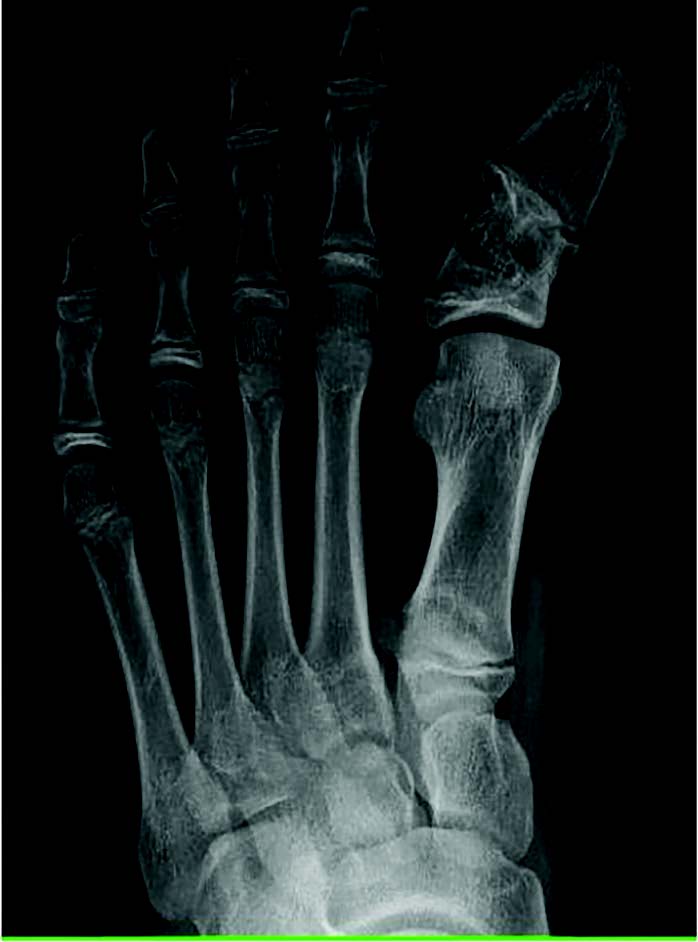

The literature traditionally presents idiopathic hallux varus as a rare clinical entity.1,2 Unfortunately, there is currently a paucity of literature related to idiopathic hallux varus, with iatrogenic hallux varus appearing more frequently in publications. Over 30 years of tracking clinical and radiographic cases, I have amassed encounters of over 700 cases of idiopathic hallux varus. We have catalogued 153 cases within our radiographic database at Ft. Leonard Wood in the last 5 years. Many would think hallux varus to be a severe deformity (see left two images below), but in reality, most of what we all tend to see is less extreme (see right image below).

Secondary hallux varus typically relates to great toe polydactyly, a delta phalanx, longitudinal epiphyseal bracket syndrome, and metatarsus adductus (see images above).6 Historically, there is also mention of a tertiary type, associated with severe skeletal abnormalities such as diastrophic dwarfism.7 Unfortunately, the literature is sparse regarding pediatric hallux varus, but within my pediatric population we see kids developing hallux varus who do not have a history of metadductus or even a spastic abductor (see images below).

Within our database, to date, we have not seen a negative intermetatarsal angle in any idiopathic hallux varus case. We routinely see normal intermetatarsal angles and often see some greater than 10 degrees. We routinely see normal sesamoid positions. In our experience, the deformity is almost always a negative PASA deformity. For iatrogenic, it seems like everyone focuses on the sesamoids, but there can be multiple permutations of sesamoid shape, position, or even lack of sesamoids. I then wondered if metatarsal length played a role, but my archives show multiple cases with short and long first metatarsals (see images below). All have the same etiology, incongruent first MTPJ, and negative PASA.